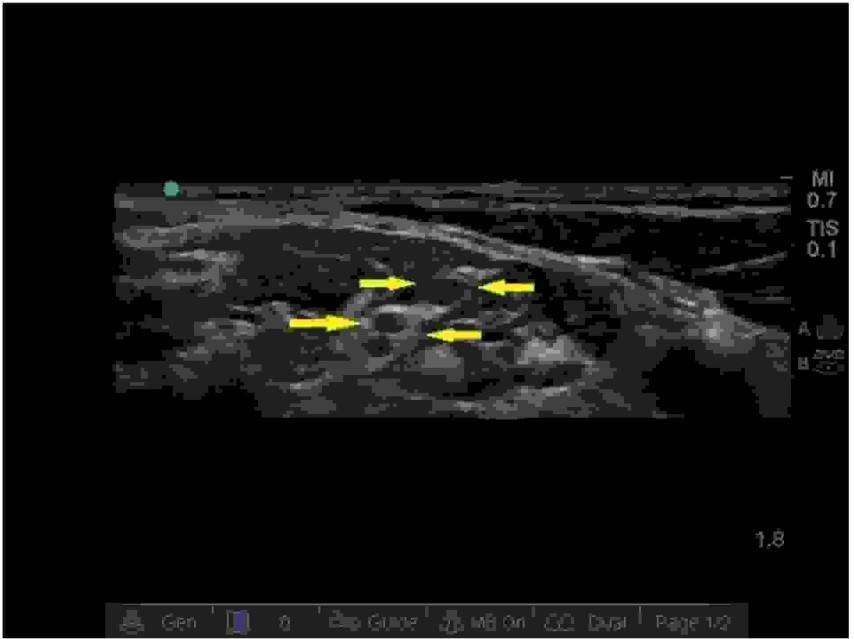

Widoczne na załączonym zdjęciu horyzontalne artefakty zaznaczone białymi strzałkami obecne w badaniu ultrasonograficznym płuc to:

Wykorzystanie ultrasonografii stanowi złoty standard w blokadach nerwów splotów. Jaką strukturę sonoanatomiczną oznaczono strzałkami na poniższym zdjęciu?